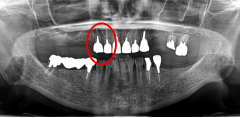

Before

赤丸2本は、歯根破折を起こしていたため抜歯しました。